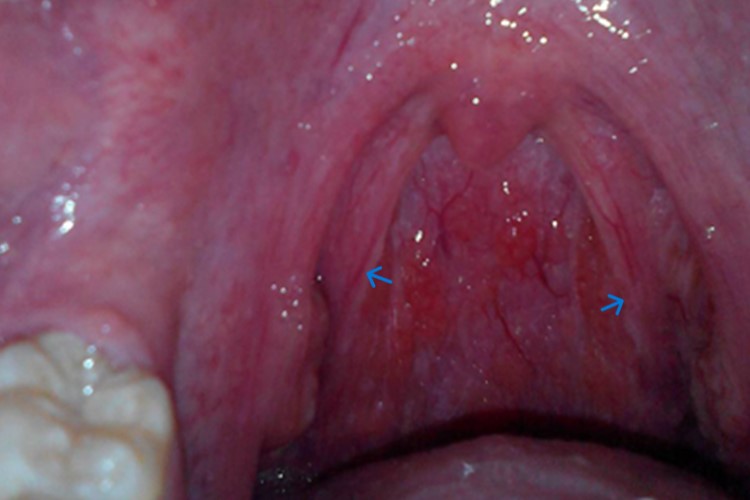

扁桃体纤维化是慢性扁桃体炎的一种,指腺体萎缩后变得小而硬,常与腭弓及扁桃体周围组织粘连,伴有咽痛、咽干、发痒等症状,还可出现吞咽、声音嘶哑、言语共鸣的障碍。

扁桃体纤维化属于慢性扁桃体炎,多由反复发作的急性扁桃体炎导致,也可继发于猩红热、白喉、流感、麻疹、鼻腔及鼻窦感染。反复的炎症使淋巴组织和滤泡变性萎缩,被广泛的纤维组织所取代,出现瘢痕状收缩。